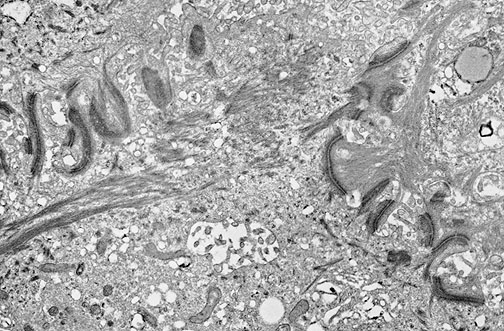

Features of a carcinoma are seen in this electron micrograph. This squamous cell carcinoma demonstrates many

desmosomes

, along with cytoplasmic

tonofilaments

streaming to the left.